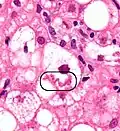

Two foci of lobular inflammation.

The primary characteristic of MASLD is the accumulation of lipids in the liver, largely in the form of triglycerides.[22] However, the mechanisms by which triglycerides accumulate and the reasons that accumulation can lead to liver dysfunction are complex and incompletely understood.[22][51][52] MASLD can include steatosis along with varied signs of liver injury: either lobular or portal inflammation (a form of liver injury) or ballooning degeneration. Similarly, NASH can include histological features such as portal inflammation, polymorphonuclear cell infiltrates, Mallory bodies, apoptotic bodies, clear vacuolated nuclei, microvesicular steatosis, megamitochondria, and perisinusoidal fibrosis.[16] Hepatocyte death via apoptosis or necroptosis is increased in MASH compared with simple steatosis, and inflammation is a hallmark of MASH.[36] The degree of inflammation can be correlated to the number of inflammatory foci. Various definitions exist for an inflammatory focus, but one defines it as the presence of more than four mononuclear cells in close proximity inside the hepatic parenchyma.[53]

NAFLD comprises two histological categories: NAFL, and the more aggressive form NASH. The presence of at least 5% fatty liver is common to both NAFL and NASH, but the features of substantial lobular inflammation and hepatocyte injuries such as ballooning or Mallory hyaline only occur in NASH. The majority of NAFL cases show minimal or no inflammation.[3][5][7] Pericentral and perisinusoidal fibrosis occur more often in adult-onset NASH, whereas portal fibrosis is more common in children with the disorder. NASH represents a more advanced stage of NAFL and is associated with poor outcomes such as cardiovascular events, cirrhosis, or hepatocellular carcinoma. ICD-11 does not use the term NAFL as it was deemed confusing with the family of disorders NAFLD. The preferred descriptions are instead: NAFLD without NASH or simple steatosis and "NASH". Also, the modifier with or without fibrosis or cirrhosis completes the diagnostic description.[3][7]